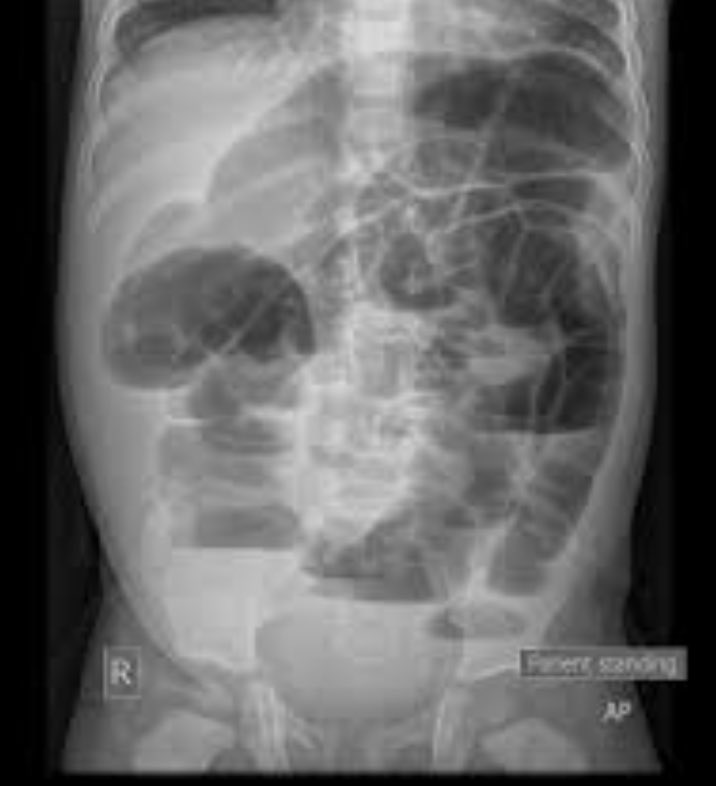

Very proud to publish this research with @ZielinskiTrauma at the @MayoClinic. "Small Bowel Obstruction Managed Without hospital admission: A Safe Way to Reduce Both Cost and Time in the Hospital?". Check it out here